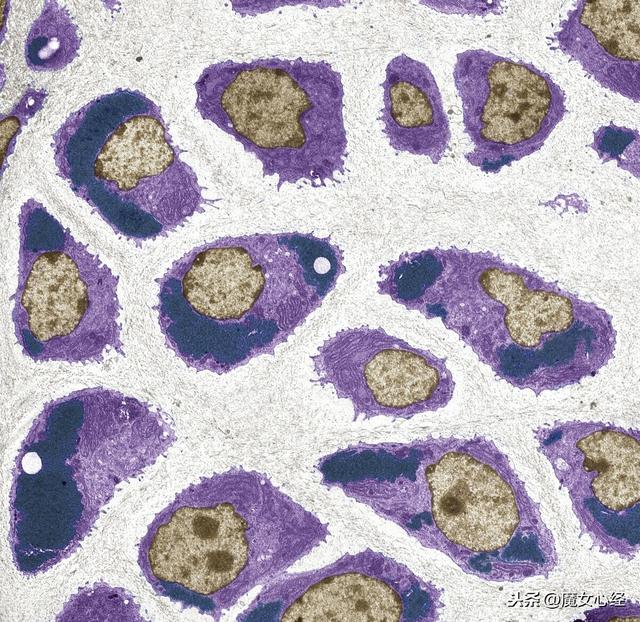

鏄惧井闀滀笅鐨勭粨缂旂粍缁囷紙鐨偆锛夛紝绱壊閮ㄥ垎鏄粏鑳烇紝閫忔槑閮ㄥ垎娌℃湁缁嗚優锛屽厖鏂ョ潃姘ㄥ熀鑱氱硸銆佽泲鐧借仛绯栥€佽兌鍘熻泲鐧界瓑鐗?/p>

鏄惧井闀滀笅杩涗竴姝ユ斁澶у悗锛屼細鍙戠幇缁嗚優涔嬮棿鍏呮枼鐫€娑蹭綋锛屽嵆缁嗚優澶栧熀璐?/p>